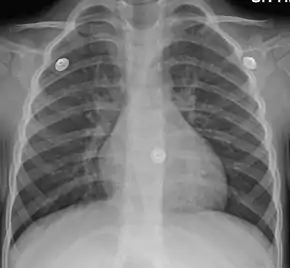

Mild peribronchial cuffing as seen in viral bronchitis

In more than 90% of cases, the cause is a viral infection.[1] These viruses may be spread through the air when people cough or by direct contact.[2] Risk factors include exposure to tobacco smoke, dust, and other air pollution.[2] A small number of cases are due to high levels of air pollution or bacteria such as Mycoplasma pneumoniae or Bordetella pertussis.[1][9] Diagnosis is typically based on a person's signs and symptom.[4] The color of the sputum does not indicate if the infection is viral or bacterial.[1] Determining the underlying organism is typically not needed.[1] Other causes of similar symptoms include asthma, pneumonia, bronchiolitis, bronchiectasis, and COPD.[1][7] A chest X-ray may be useful to detect pneumonia.[1]